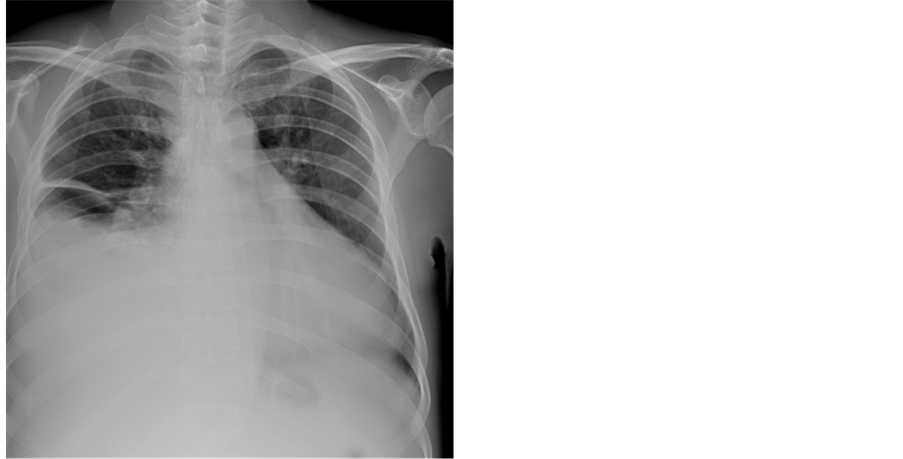

Figure 77. X-ray chest PA (postero-anterior view) showing right sided pleural effusion and cardiomegaly suggesting the aneurysmal LV (left ventricle) in RV EMF in a 42-year-old male.

Endocardial calcific deposits can be present, involving diffuse areas of the ventricles and Cockshott et al. described this feature in 1967. Calcification, an impressive finding on imaging denotes a burnt-out phase of endomyocardial fibrosis (EMF) and confirming the malignant nature of the disease. Chest X-rays show varying degrees of cardiomegaly and at times typical endocardial calcifications in the left and right ventricles as shown in Figure 9 (left ventricular endocardial calcification) ( [24] , Figure 2(a)) and in Figure 16 (right ventricular endocardial calcification) ( [25] , Figure 2(c) shows calcification in both ventricles) [26] .

A large pericardial effusion is often present and noted as another peculiar feature of this disease [27] . Pericardial effusion and ascites dominate the clinical picture of right ventricular EMF [28] [29] [30] . Etiology of pericardial effusion is possibly inflammatory and EMF is to be considered as “pancarditis” since all the layers are involved. Adhesions between the parietal and visceral layers of the pericardial sac may develop and visible as strong fibrotic strands as shown in Figure 29. A right ventricular EMF presented with massive pericardial effusion was detected in a 85-year-old female as shown in Figure 16, Figure 17 and Figure 18 [31] . Cardiomegaly can be exaggerated by pericardial effusion, and pleural effusion is also a common finding as shown in Figure 9 ( [16] , Figure 2).